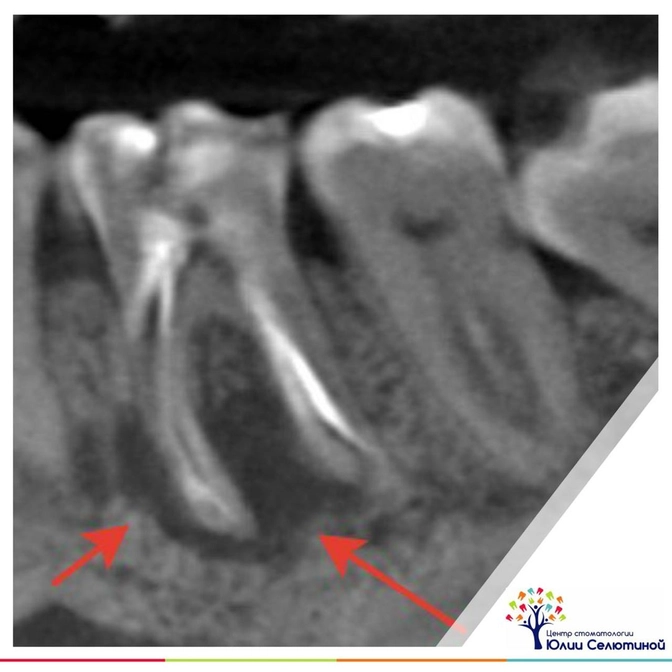

На снимке видно область затемнения — это уже полость, которая образовалась на месте растворенной костной ткани.

Чем она больше, тем дольше времени понадобится для восстановления, иногда это несколько лет.